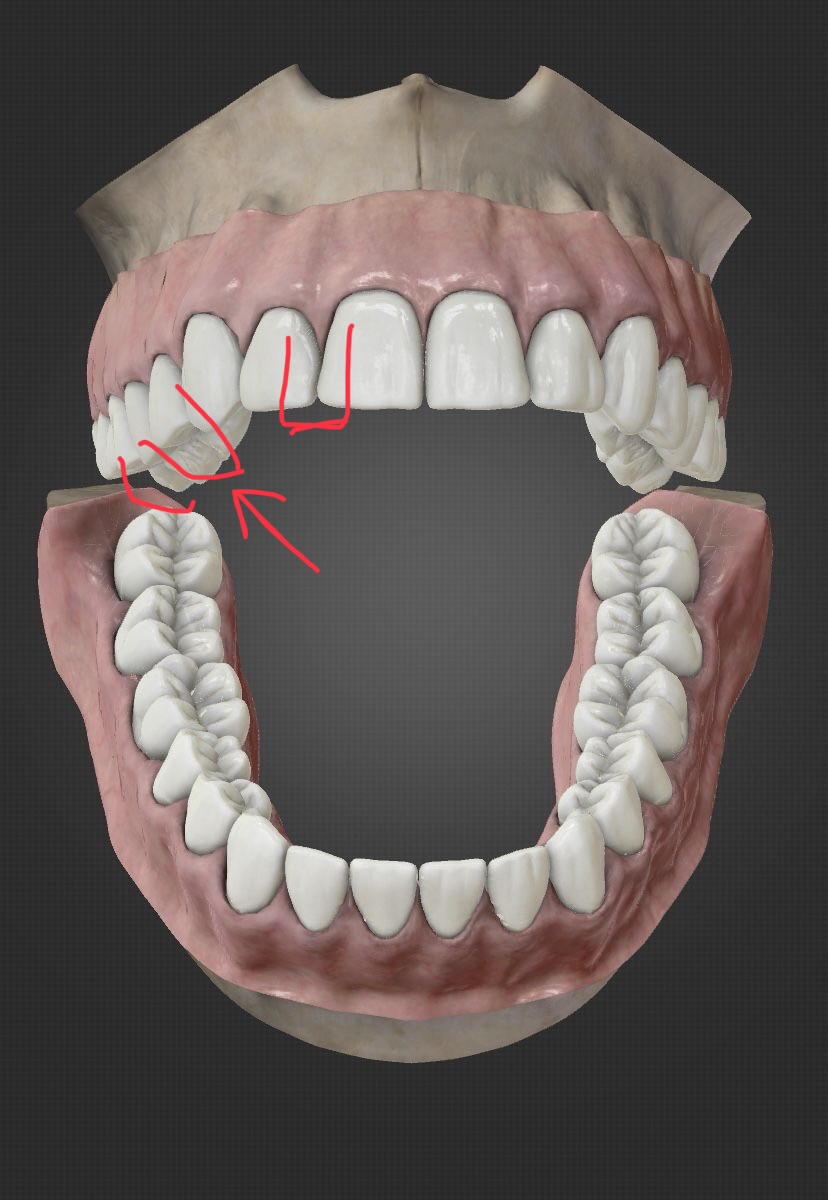

Ананасы подскажите пожалуйста

Сегодня ходил лечить пульпит, шестерку нижнюю, почистили каналы и поставили временную пломбу. Пломбу не фоткал как она была до. Было ощущение что при закрытии рта верхние зубы чуть-чуть опирались на зуб с пломбой, понял это уже только когда ебало от наркоза медленно начало отходить. Через четыре часа поел чуть теплого супчика с мягчайшими тефтельками, это был первый прием пищи после пломбирования, и понял что почему то верхние зубы снизу опоры больше не ощущают. Как будто часть пломбы отвалилась. Фотки прикрепляю.